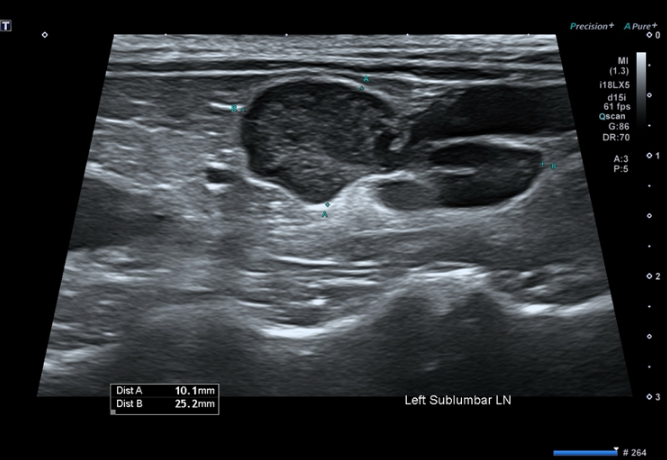

그림 1. 복부 초음파에서 확인된 요추하 림프절 비대

체표 및 복강 내 다발성 림프절 비대 확인

비장에서 벌집 징후(honeycomb sign) 관찰